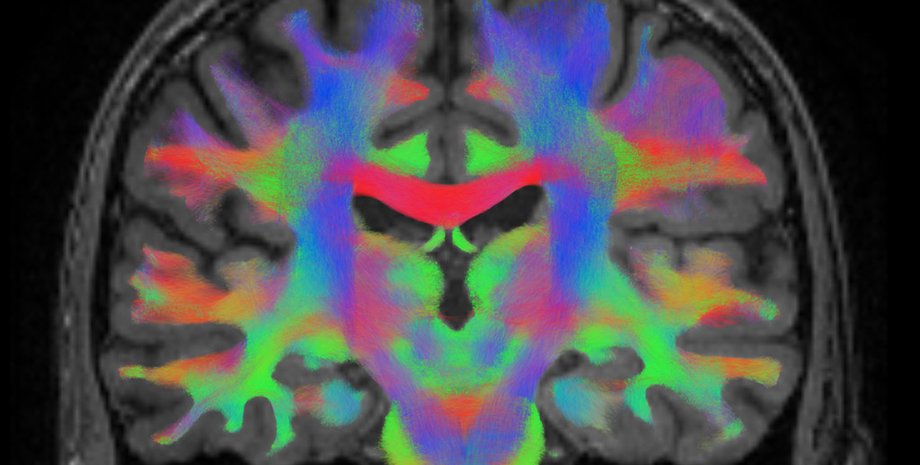

Делали они это во время сканирования мозга с помощью функциональной магнитно-резонансной томографии (фМРТ). Чем больше участники подавляли сверхъестественное мышление, тем сильнее была активация правой нижней лобной извилины. Эта область мозга связана с когнитивным торможением, способностью воздерживаться от определенных мыслей и поведения.